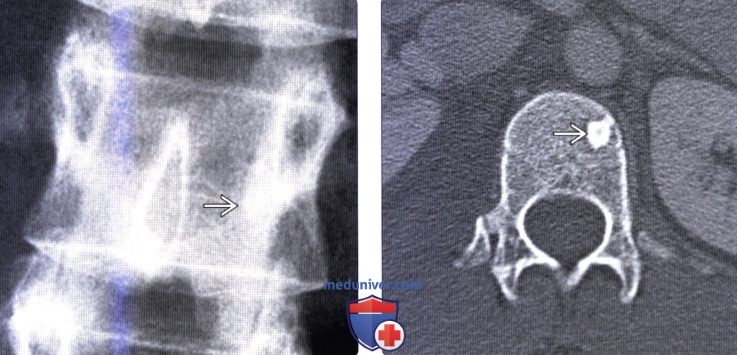

Рентгеновские снимки остеосклероза костной ткани